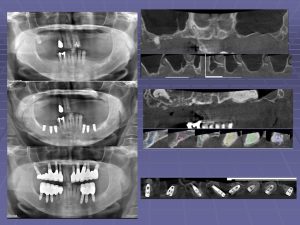

「脊柱管狭窄症について」

川植康史会員